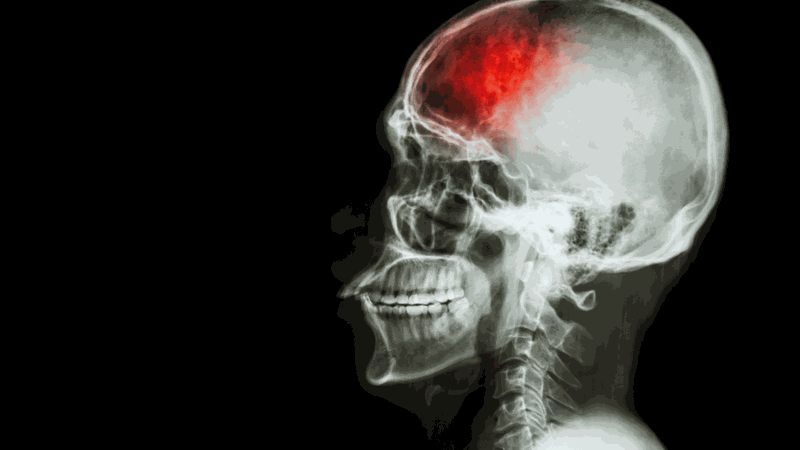

Đột quỵ là tình trạng nguy hiểm xảy ra khi dòng máu lên não bị gián đoạn, gây tổn thương nghiêm trọng. Nguyên nhân có thể do huyết áp cao, tiểu đường, bệnh tim hoặc thói quen sống không lành mạnh. Vậy nguyên nhân gây đột quỵ là gì? Cùng tìm hiểu qua bài viết dưới đây.

Đột quỵ là một trong những nguyên nhân hàng đầu gây tử vong và tàn tật trên toàn cầu. Bệnh xảy ra khi dòng máu lên não bị gián đoạn, làm tổn thương các tế bào não chỉ trong vài phút. Có nhiều nguyên nhân dẫn đến đột quỵ, từ cao huyết áp, tiểu đường, bệnh tim mạch đến lối sống không lành mạnh. Tuy nhiên, đột quỵ hoàn toàn có thể phòng ngừa nếu bạn nhận thức đúng và áp dụng các biện pháp kiểm soát yếu tố nguy cơ. Vậy nguyên nhân gây đột quỵ là gì và làm thế nào để giảm thiểu rủi ro? Hãy cùng Long Châu tìm hiểu trong bài viết sau.

Đột quỵ, còn gọi là tai biến mạch máu não, là tình trạng cấp cứu y tế xảy ra khi dòng máu lên não bị gián đoạn hoặc giảm đột ngột, dẫn đến tổn thương tế bào não do thiếu oxy và dưỡng chất. Nếu không được can thiệp kịp thời, đột quỵ có thể gây ra hậu quả nghiêm trọng như suy giảm chức năng thần kinh, tàn tật vĩnh viễn hoặc tử vong.